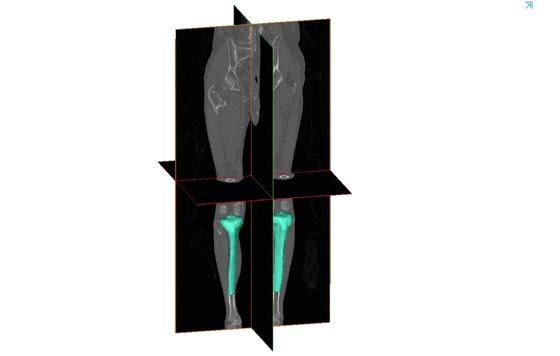

Para intentar mejorar esta situación, el Instituto de Biomecánica (IBV) está desarrollando el proyecto RECBONE, financiado por el Instituto Valenciano de Competitividad Empresarial (IVACE) y cofinanciado por la Unión Europea, con el que avanza en el diseño y la fabricación de productos sanitarios para la reconstrucción osteoarticular y la generación de modelos anatómicos, mediante la combinación de tecnologías como la impresión 3D y la Inteligencia Artificial (IA).

IBV ha desarrollado metodologías novedosas que permiten utilizar los modelos anatómicos en campos tales como la cirugía ortopédica y traumatología, dental o craneomaxilofacial.

Este experto añade que, a título de ejemplo, “se han aplicado estas metodologías de segmentación y obtención de modelos anatómicos a la cirugía de reemplazo de rodilla, desarrollando guías quirúrgicas a medida para realizar las osteotomías de tibiales en el proceso de implantación de la prótesis de rodilla. Esta técnica mejora notablemente los resultados de las cirugías al asegurar el correcto posicionamiento de la prótesis durante la cirugía”.